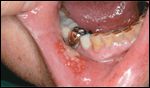

Chemotherapy-induced mucositis with ulcerations of the mucous membranes. Image courtesy of Christiane Querfeld, MD FIGURE 2

Oral mucositis occurring during week 4 of radiation treatment. (Dose was 45 Gy; patient did not receive chemotherapy.) Image courtesy of Sol Silverman, DDS

Signs and symptoms of chemotherapy- or radiation-induced OM are the same for Mrs. S. and Mrs. J. The physical appearance is indistinguishable (see Figures 1 and 2). Bright erythema of the oral mucosa, edema, patches of denuded epithelium, elevated white desquamative patches, and ulcers may be seen in the oral cavity.[5] All of these signs are dose-limiting. Patients may report pain or burning sensations in the oral cavity, and increased sensitivity to hot or spicy foods.[5]